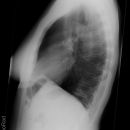

Abdomen

Freie Luft Linksseitenlage